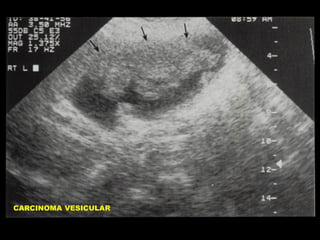

APARIENCIA ECOGRAFICA DEL

CARCINOMA DE VESICULA

•

Masa intraluminal

Engrosamiento mural asimétrico

Masa reemplazando la Vesícula

Calcificación de la pared Vesicular

Colelitiasis

Metástasis Hepáticas

Adenopatías

Dilatación de la via biliar

CA VESICULAR

CARCINOMA VESICULAR